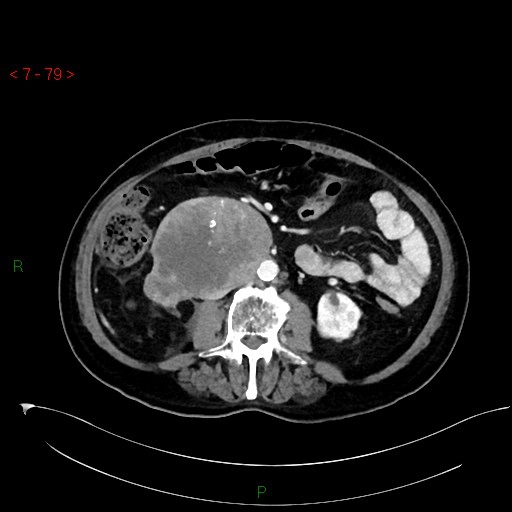

Sarcoma mỡ sau phúc mạc (Retroperitoneal liposarcoma)

16/03/2026